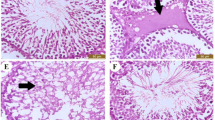

Regarding results of the immunohistochemical, there was a dramatic up-regulation of caspase-3 either cytoplasmic or nuclear expression in the hepatic and renal tissues caused by CP (Fig. 3 and 4, respectively). On the other side, caspase-3 expressions slightly up-regulated in contrast to the control group were found in the LP + CP and NAC + CP groups. Moreover, the CP-mediated caspase-3 up-regulation reduced sharply by combined treatment of LP and NAC.

Changes in hepatic caspase-3 expression. (a)–(c) showed the negative immunostaining reactions in the Control (a), LP (b), and NAC (c) groups. (d) and (e) CP-induced changes showing severe immunostaining reaction. (f) Caspase staining in the LP + CP group showing moderate immunostaining. (g) Caspase staining in the NAC + CP group showing moderate immunostaining. (h) Caspase staining in the LP + NAC + CP group showing mild immunostaining. Scale bar = 50 μm.

Changes in renal caspase-3 expression. (a)–(c) showed the negative immunostaining reactions. (a). Control group showing very mild caspase-3 immunostaining. Caspase-3 staining in the LP (b) and NAC (C) groups showing the negative immunostaining reaction. (d) and (e) treated group with CP showed severe immunostaining reaction. (f) Caspase staining in the LP + CP group showing moderate immunostaining. (g) Caspase staining in the NAC + CP group showing moderate immunostaining. (h) Caspase staining in the LP + NAC + CP group showing mild immunostaining. Scale bar = 50 μm.